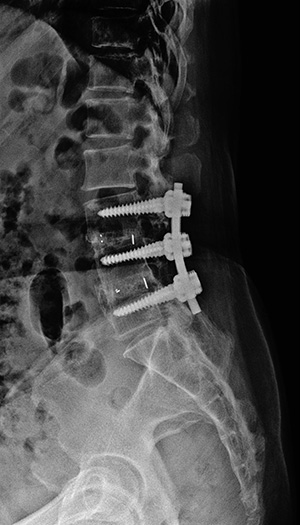

▼ 척추뼈 2개를 묶은 유합술 ▼

유합술 측면 X-ray